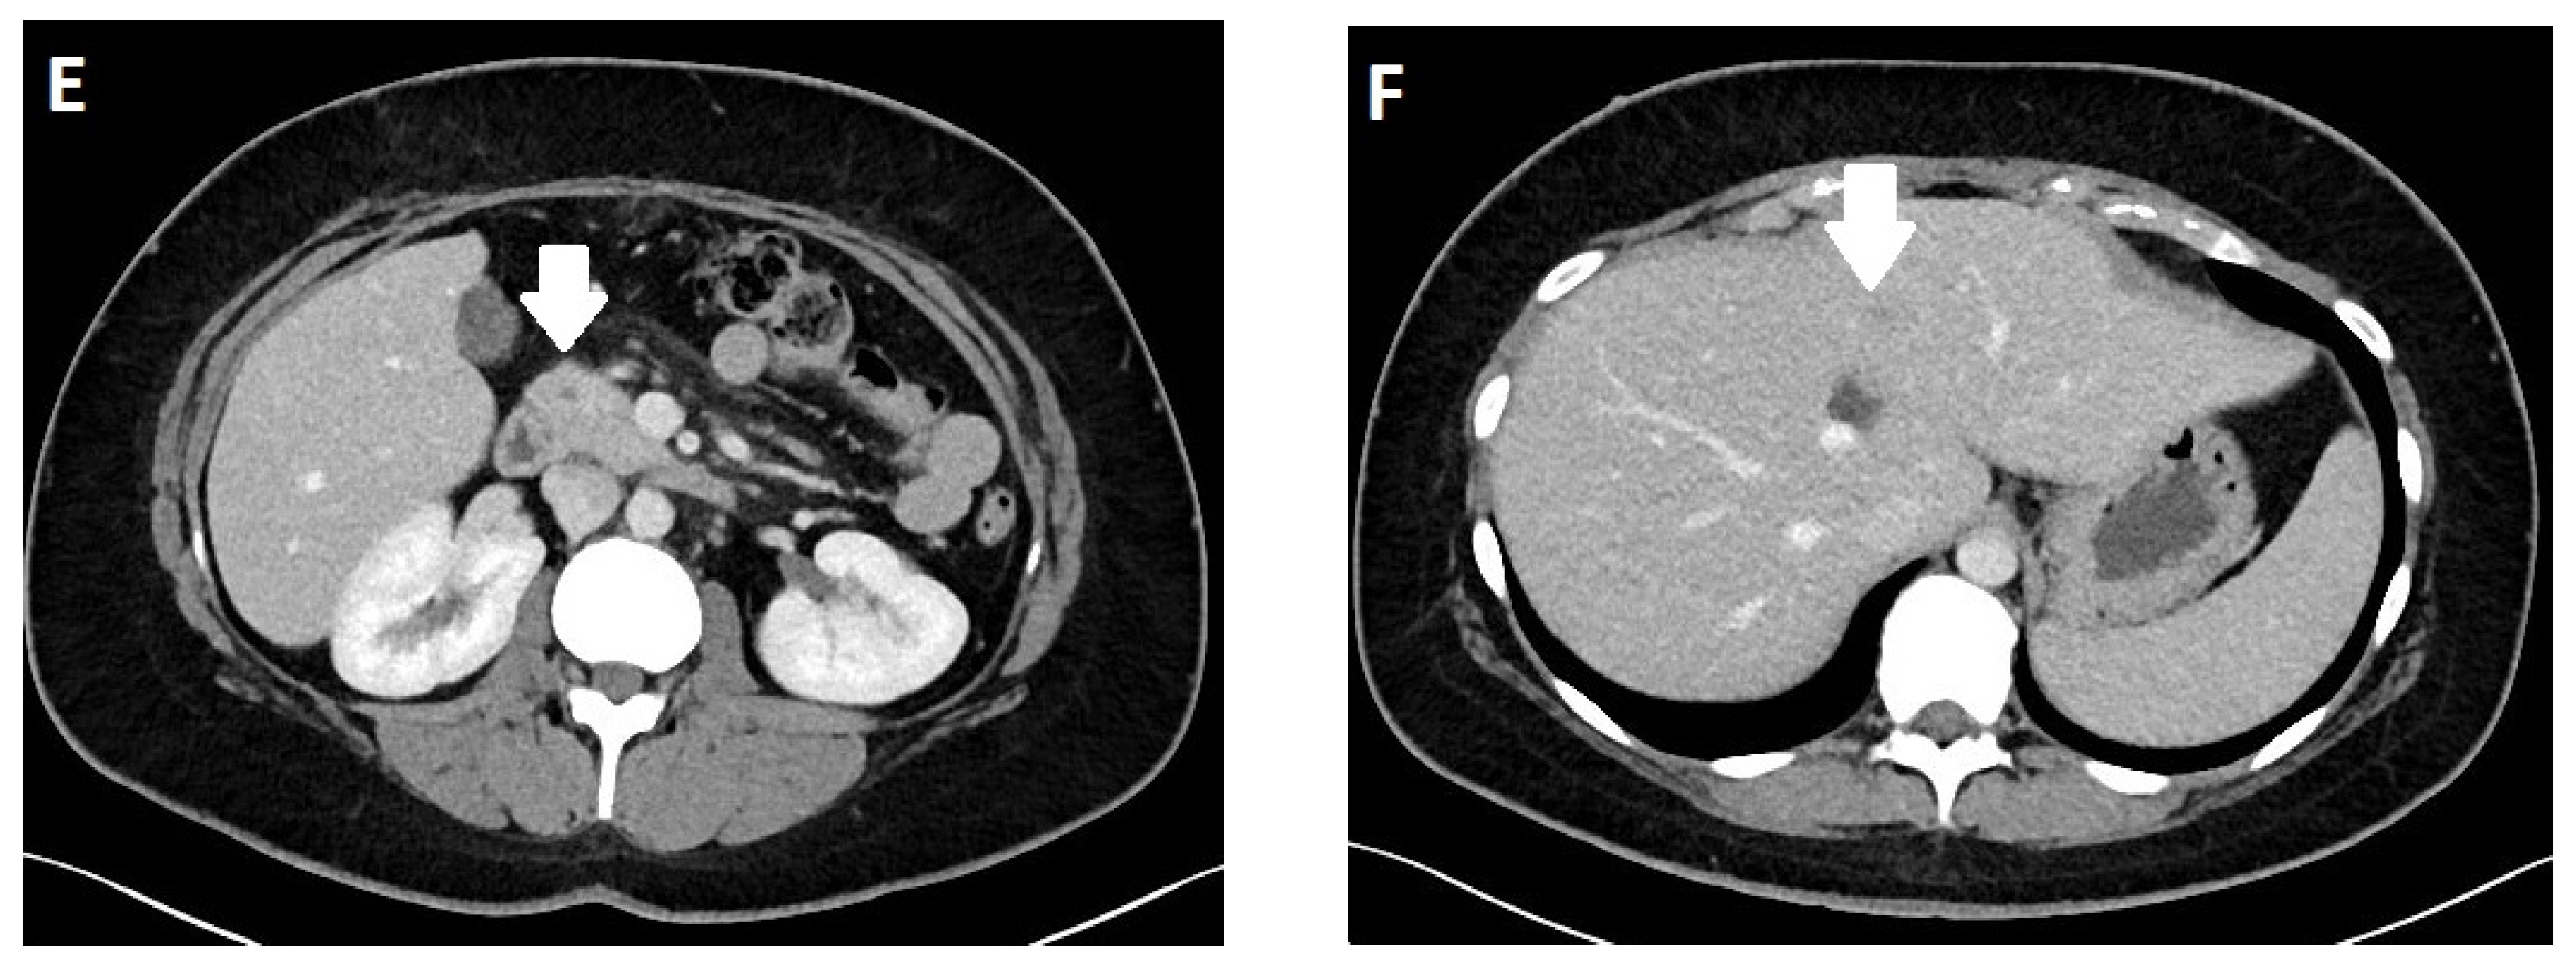

3.4. Imaging

- Kim, J.H.; Eun, H.W.; Kim, Y.J.; Lee, J.M.; Han, J.K.; Choi, B.I. Pancreatic neuroendocrine tumour (PNET): Staging accuracy of MDCT and its diagnostic performance for the differentiation of PNET with uncommon CT findings from pancreatic adenocarcinoma. Eur. Radiol. 2016, 26, 1338–1347. [Google Scholar] [CrossRef] [PubMed]

- Lee, L.; Ito, T.; Jensen, R.T. Imaging of pancreatic neuroendocrine tumors: Recent advances, current status, and controversies. Expert. Rev. Anticancer. Ther. 2018, 18, 837–860. [Google Scholar] [CrossRef]

- Bicci, E.; Cozzi, D.; Ferrari, R.; Grazzini, G.; Pradella, S.; Miele, V. Pancreatic neuroendocrine tumours: Spectrum of imaging findings. Gland. Surg. 2020, 9, 2215–2224. [Google Scholar] [CrossRef]

- Sundin, A.; Arnold, R.; Baudin, E.; Cwikla, J.B.; Eriksson, B.; Fanti, S.; Fazio, N.; Giammarile, F.; Hicks, R.J.; Kjaer, A.; et al. ENETS Consensus Guidelines for the Standards of Care in Neuroendocrine Tumors: Radiological, Nuclear Medicine & Hybrid Imaging. Neuroendocrinology 2017, 105, 212–244. [Google Scholar] [CrossRef] [PubMed]